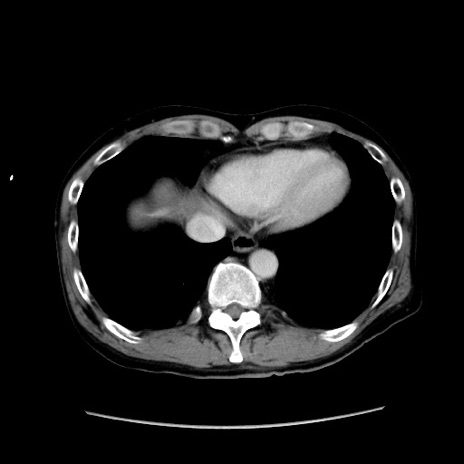

冠状断像

【症例】40歳代 男性

【主訴】腹痛

【現病歴】4時間ほど前に電車に乗車中に臍部上より腹痛出現。徐々に増悪し起立困難となり、救急外来受診。生ものは数日食べていない。今朝お雑煮を食べた。

【身体所見】BT 36.8℃、BP 117/84mmHg、HR 91/min、SpO2 97%、苦悶様、腹部:臍上部広範囲圧痛あり、反跳痛±

【データ】WBC 8100、CRP 0.03